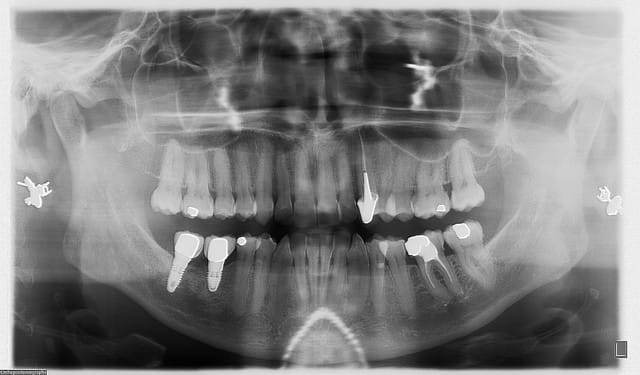

bon, voilà...

patiente de 45 ans, nouvelle pour moi...mais patiente du cab depuis plus de 30 ans (c'est mon père qui l'avait suivie, soins ODF, etc...)

pour raisons professionnelles, elle est partie en Asie pendant près de 10 ans...

par manque de chance, elle s'est explosé la 46 et la 47 (fracture verticale) sur un noyau...extractions, greffe osseuse, implants que j'avais remarqué lors de l'examen intrabuccal du fait du profil d'émergence caractéristique des couronnes

le travail a été réalisé il y a 5 ans, elle ne connaît pas la marque des implants...

pano de contrôle, c'est "propre", j'identifie au premier coup d'oeil la marque mais contrôle en live sur le site whatthisimplant l'image radio pour être sûr à 100%...c'est bien çà c'est du Nobel replace tapered...

je lui dis que je peux assurer le suivi mais pas la garantie du travail qui a été réalisé à Singapour (elle comprend parfaitement...) mais que d'avoir identifié les implants est un plus en cas de bris de céram ou de dévissage ne serait-ce que pour re-commander les pièces...et que bien que je ne pose pas du Nobel, je trouverai le moyen de me procurer les tournevis adéquats pour...

détartrage, et voilà...une patiente ravie d'avoir trouvé un professionnel pour la suivre tout en connaissant mes limites, et visiblement impressionnée elle en a profité pour prendre des RDV pour toute sa famille (mari, gamins pour l'ODF...je ne crois pas que je vais perdre quelque chose...au contraire!!!) je suis sûr que si jamais il y avait un problème, elle ne se poserait même pas la question de savoir vers qui se tourner...et sans me tenir pour responsable de quoi que se soit puisque j'ai été bien clair avec elle depuis le début...